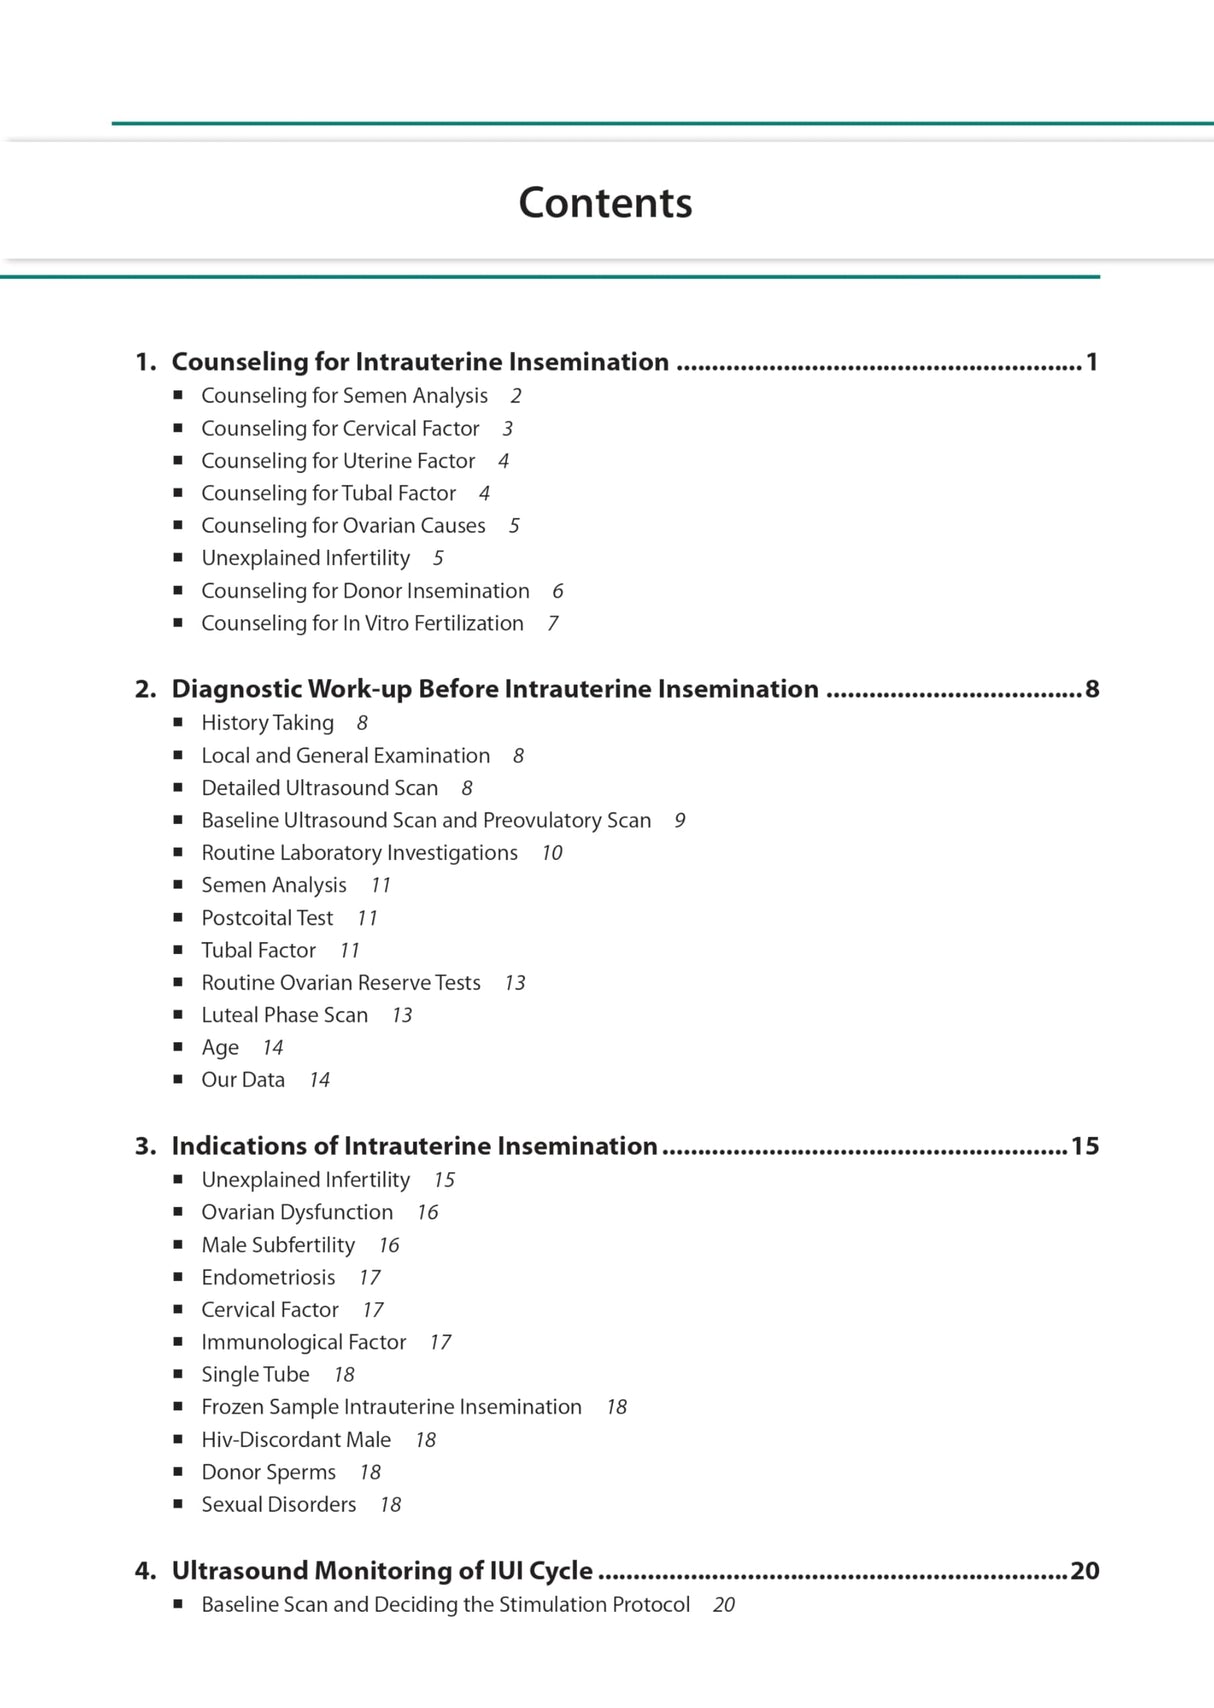

Beginning with discussion on counselling and diagnostic work-up before IUI, the next chapters cover indications and ultrasound. The following sections examine ovulation, timing of IUI, techniques, luteal phase support, complications, and factors affecting success. The final chapter discusses sperm preparation.